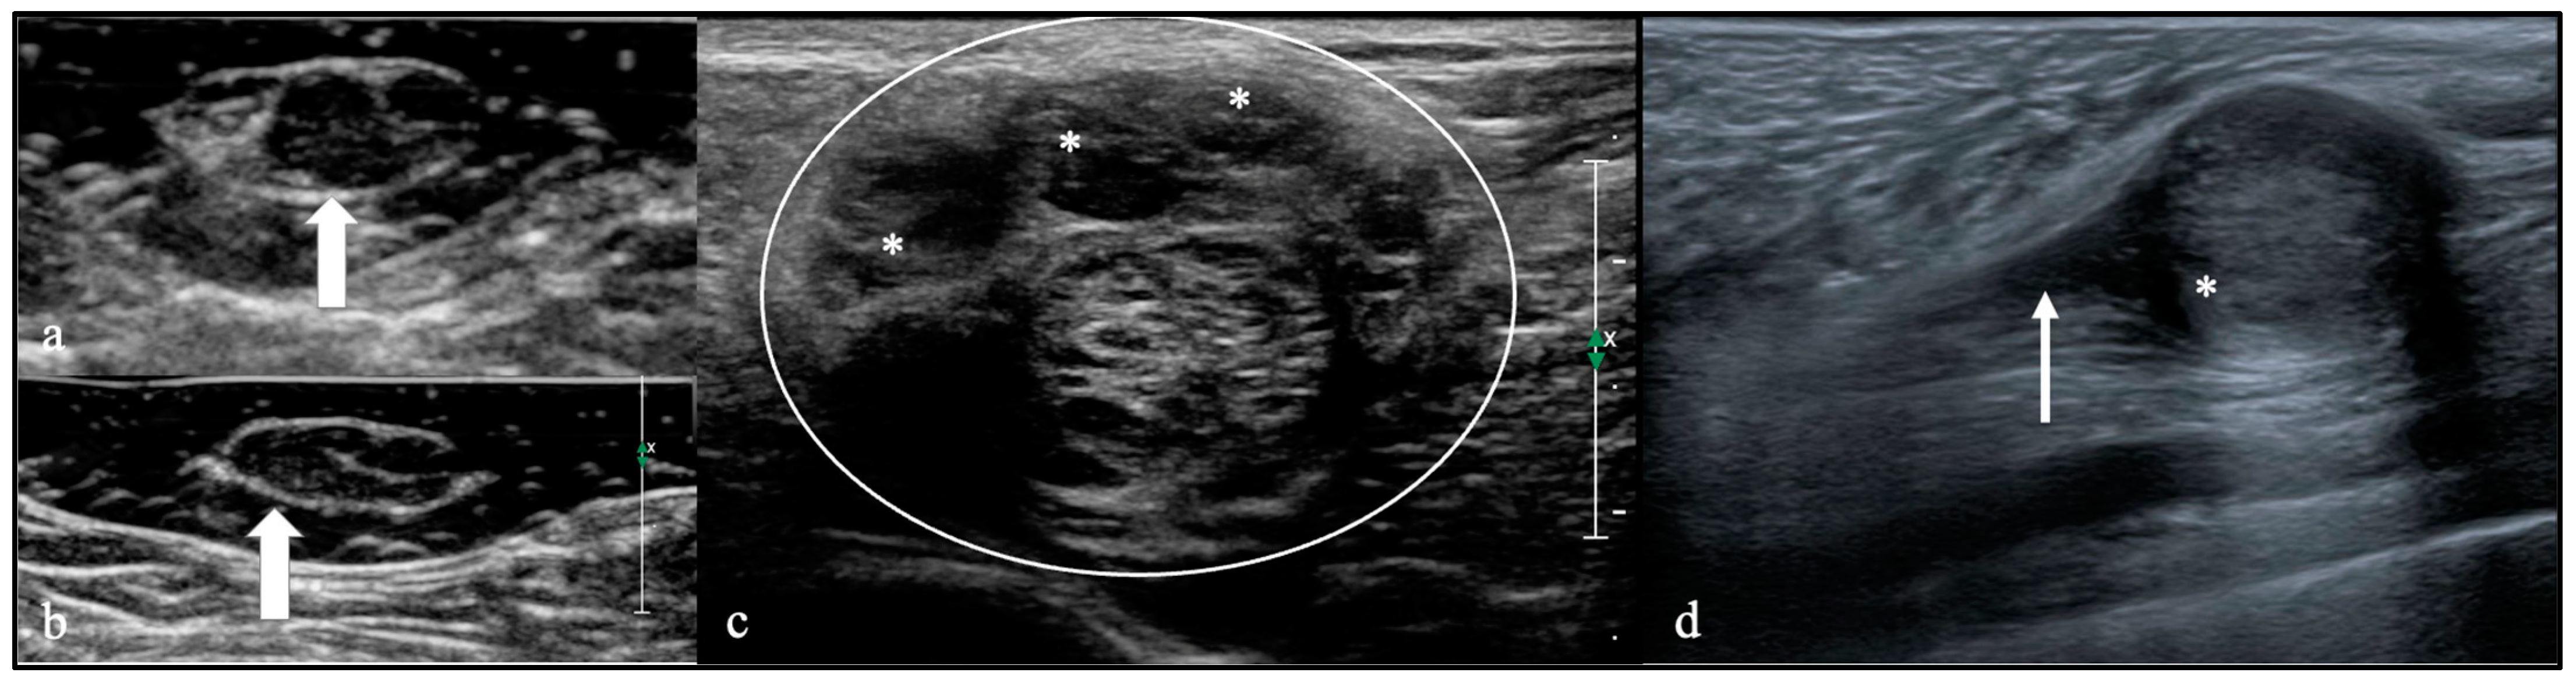

| Histopathological Diagnosis | Ultrasound | |||||

|---|---|---|---|---|---|---|

| Echogenicity | Type | |||||

| Iso (n, %) | Hypo (n, %) | Hyper (n, %) | A (n, %) | B (n, %) | C (n, %) | |

| Intrinsic PNTs | ||||||

| HPNST (S/NF) (n = 3) | 1 (33%) | 2 (67%) | 3 (100%) | |||

| MPNST (n = 7) | 1 (8%) | 6 (46%) | 7 (100%) | |||

| Perineurioma (n = 10) | 2 (20%) | 8 (80%) | 10 (100%) | |||

| ANNUBP (n = 1) | 1 (100%) | 1 (100%) | ||||

| Extrinsic PNTs | ||||||

| Lymphoma (n = 1) | 1 (100%) | 1 (100%) | ||||

| Amyloidoma (n = 1) | 1 (100%) | 1 (100%) | ||||

| Hemangioma (n = 1) | 1 (100%) | 1 (100%) | ||||

| Angiomatosis (n = 1) | 1 (100%) | 1 (100%) | ||||

| Capillary hemangioma (n = 1) | 1 (100%) | 1 (100%) | ||||

| EHE (n = 1) | 1 (100%) | 1 (100%) | ||||